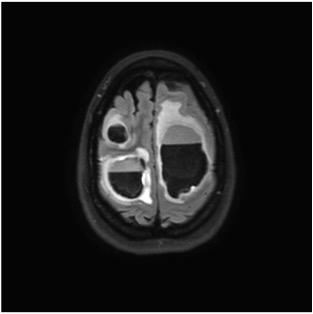

To study the hypothesis that radiation to the hippocampal stem cells plays a role in cognitive decline, 518 patients were randomized to whole-brain radiotherapy plus memantine with or without hippocampal avoidance. The results of the clinical trial found a 26 percent relative reduction in risk of cognitive toxicity following whole-brain radiation therapy with hippocampal avoidance versus whole brain radiotherapy. The cognitive function benefit of hippocampal avoidance did not differ by age.

Brain metastases, cancer cells that have spread to the brain from primary tumors in other organs, is one of the most common cancer conditions managed by radiation oncologists. Due to concerns about cognitive decline, whole-brain radiotherapy is currently often the last resort, even though it is one of the most effective treatments for brain metastases.

By establishing that the hippocampal region is sensitive to radiation, treatment plans for brain metastases or other brain tumors can employ advanced techniques such as intensity-modulated radiation therapy (IMRT) or proton therapy to reduce dose to the hippocampus and offer brain therapy with less toxicity.